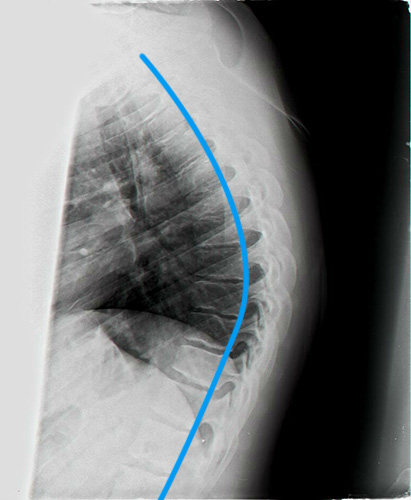

לפני ואחרי טיפול בבעיות יציבה כלליות 1

קיפוזיס שויירמן צילום לאחר 4 חודשי טיפול קיפוזיס שויירמן צילום טרום טיפול

קיפוזיס בכיפוף לפנים

קיפוזיס שויירמן לאחר חודש טיפול קיפוזיס שויירמן טרום טיפול